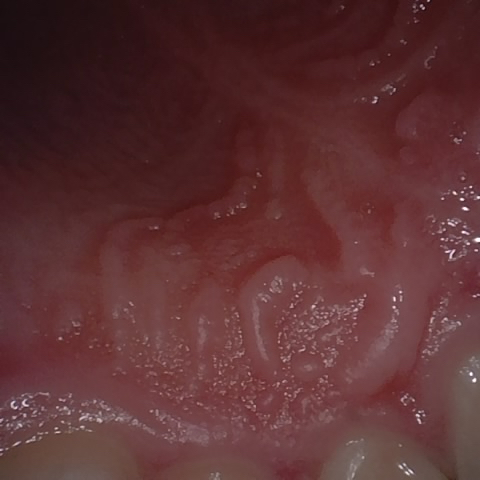

NHD39990

Annotated as "Good"

Original Image Rendering Image